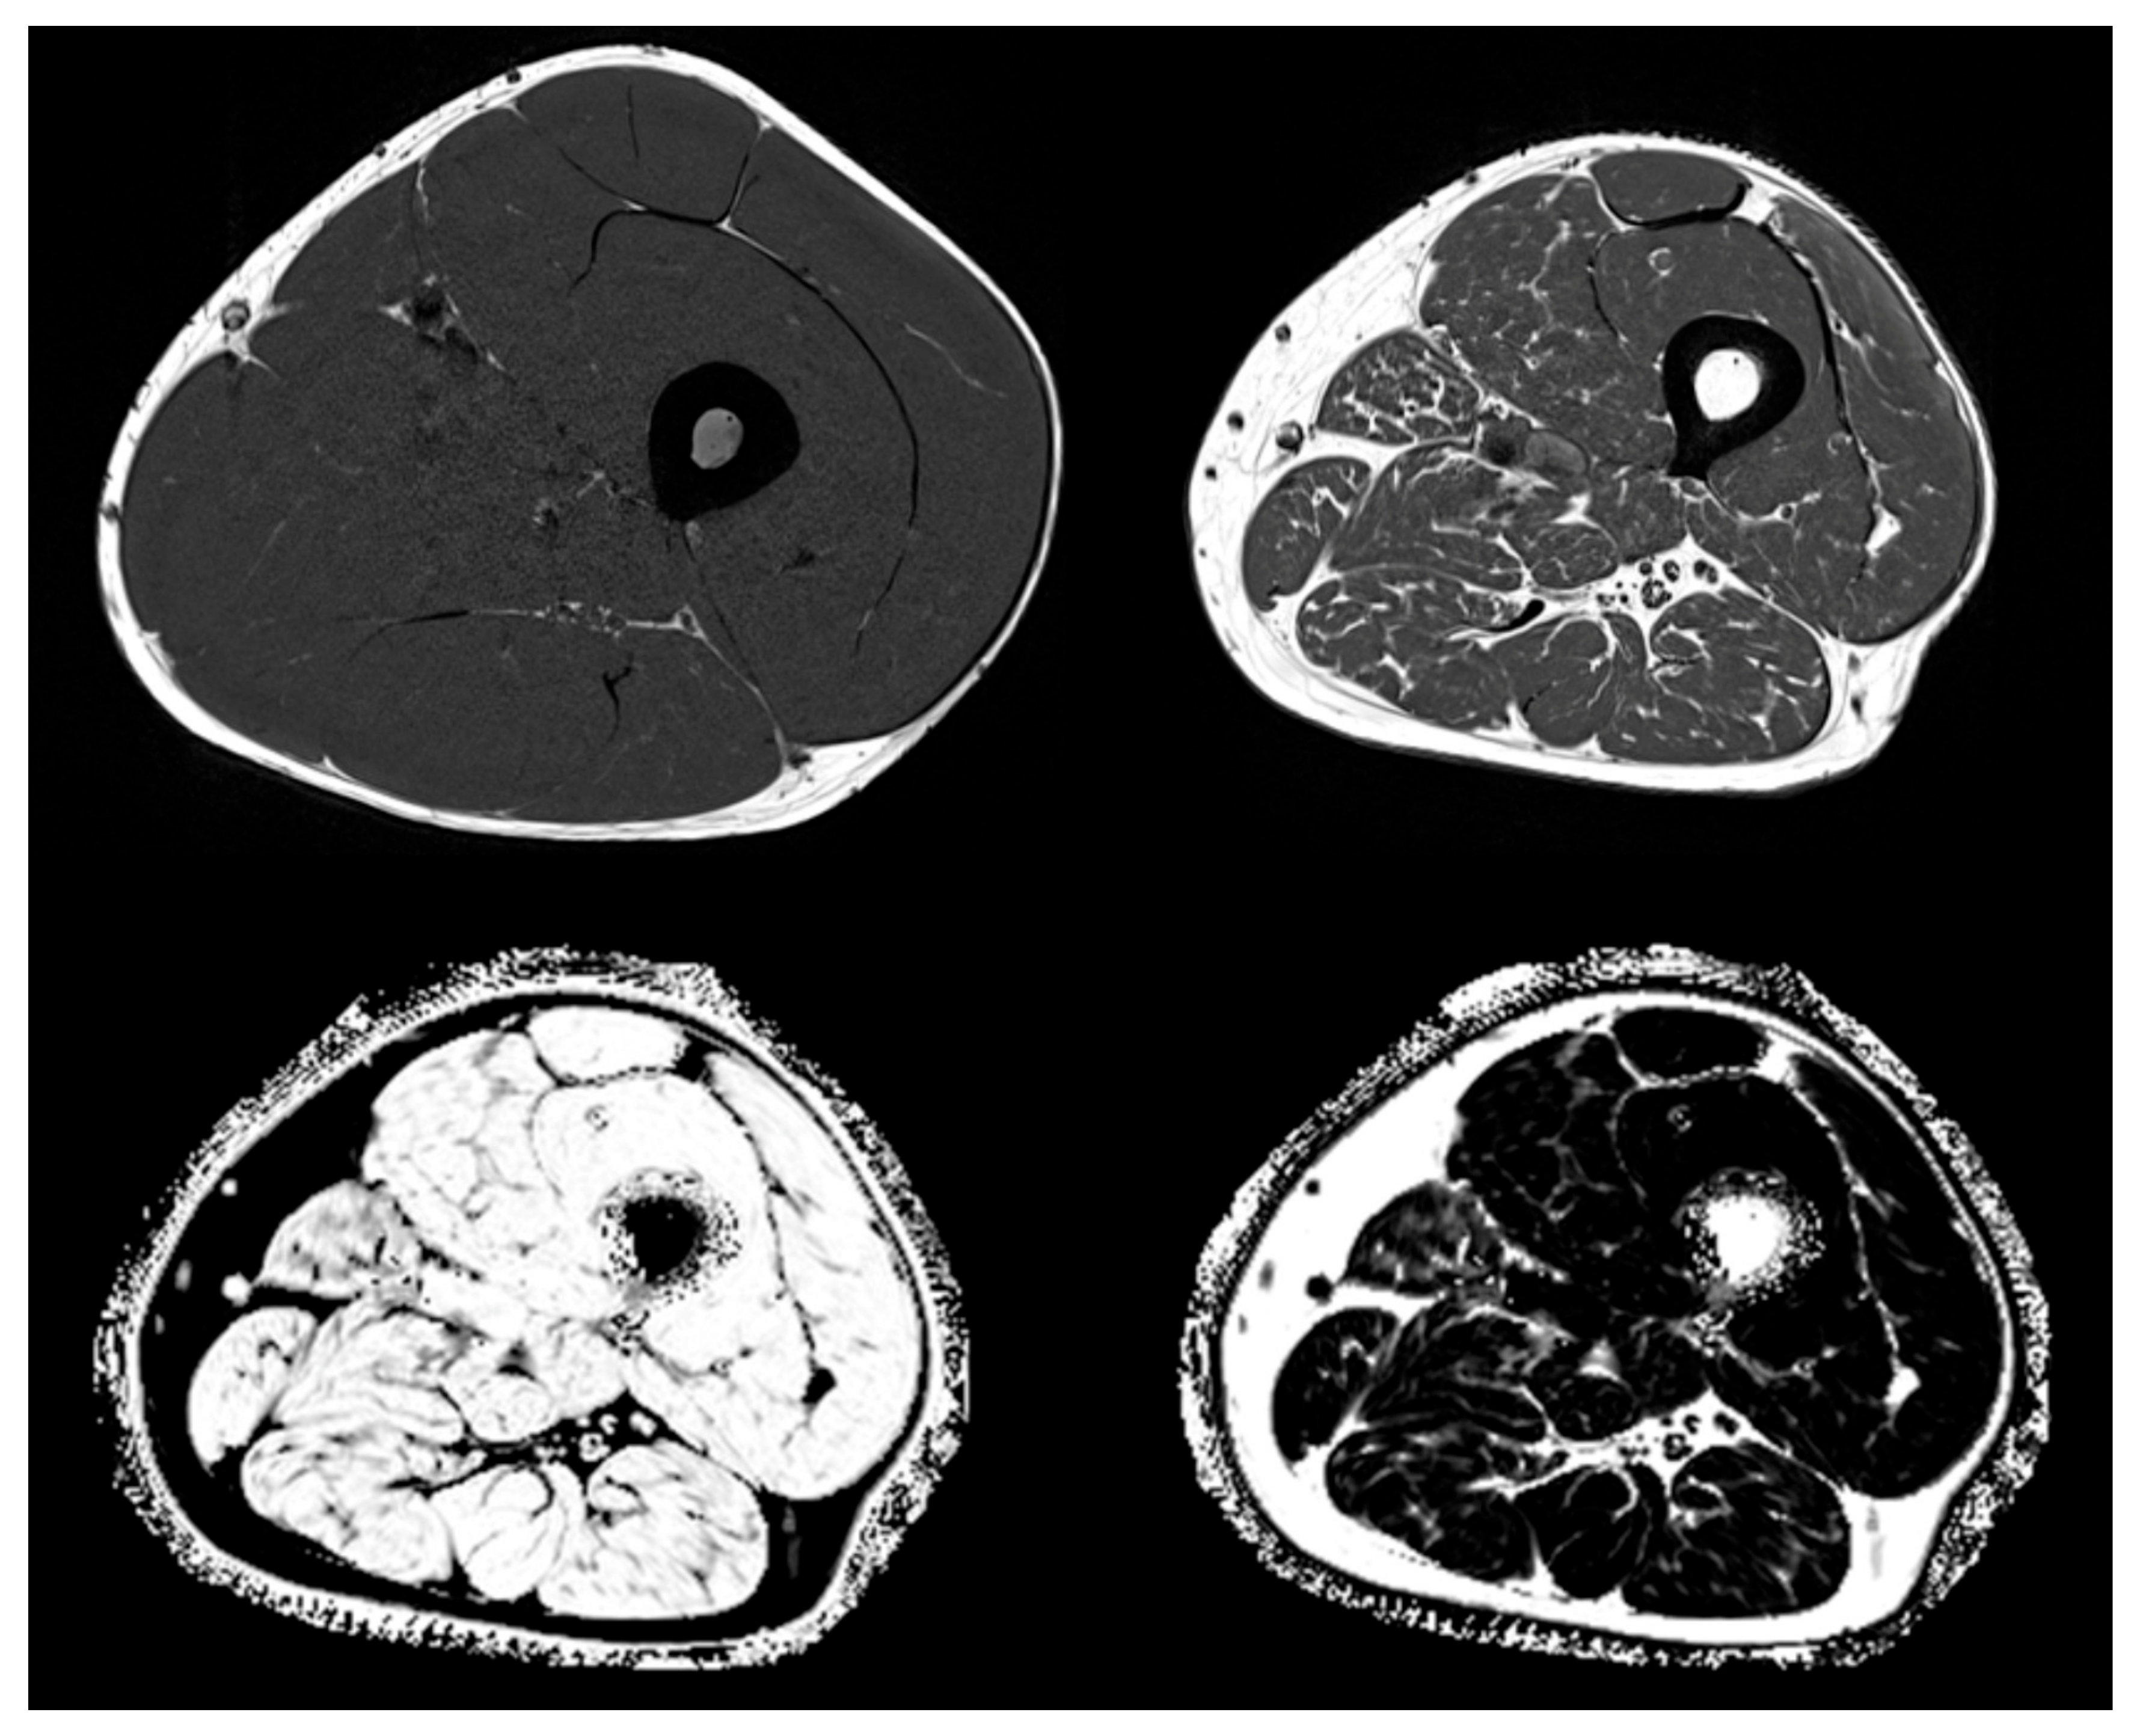

In clinical routine, the preferred method is semi-quantitative assessment of muscle and adipose tissue area or volume from T1 weighted MR images, which show very good contrast between these two tissues (see Figure 3 top left and top right showing T1 weighted images from a young healthy normal male and from an elderly male with sarcopenia). T1 images are used for the assessment of intermuscular adipose tissue (IMAT), which is the ensemble of ‘white voxels’ within the fascia lata (FL) [181]. White voxels in the T1 images show adipocyte agglomerations located between as well as within individual muscles. Within the muscles, they are located among individual muscle fibers and are often summarized as extramyocellular lipids (EMCL) in contrast to intramyocellular lipids (IMCL), which are droplets of triglycerides located within muscle cells. In essence, IMAT denotes larger agglomerations of EMCL and perimuscular adipocytes within the FL. Intra- and extramyocellular lipids, IMCL and smaller EMCL agglomerations, are not captured by IMAT as measured by MRI (Figure 4).

Figure 3.

Magnetic resonance imaging (MRI)-based muscle imaging. Weighted image of young healthy (top left) and elderly sarcopenic male (top right). Water fraction (bottom left) and fat fraction (bottom right) images of subject shown in top right.

With MR Dixon sequences that generate so-called fat and water fraction images (Figure 3 bottom) [182], the fat fraction which is the combined %fat of the analyzed VOI and can be quantified. For example, in muscle, FF reflects all EMCL and IMCL. Differentiation between these components is only possible with MR spectroscopy (MRS) [183,184], which is not an imaging method.